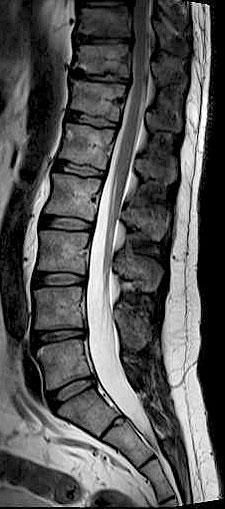

Die Kernspintomographie liefert detailgenaue Schnittbildaufnahmen des menschlichen Körpers ohne Röntgenstrahlen – und das sogar von Blutgefäßen. Bei der MRT werden Sie in einem starken Magnetfeld untersucht. Ähnlich wie bei einem Radio werden UKW-Wellen verwendet. Um dünne Schichtaufnahmen zu erzeugen, benötigen wir zusätzlich schwach wechselnde Magnetfelder, wodurch ein lautes Klopfgeräusch entsteht. Die Signale werden dann von einem sehr leistungsfähigen Computersystem zu Schichtaufnahmen in verschiedenen Ebenen umgewandelt. Die Untersuchung dauert je nach Fragestellung 7 bis 35 Minuten. Während der Messzeit sollten Sie ruhig und entspannt liegen, denn jede Bewegung verursacht Bildstörungen und verlängert die Prozedur.